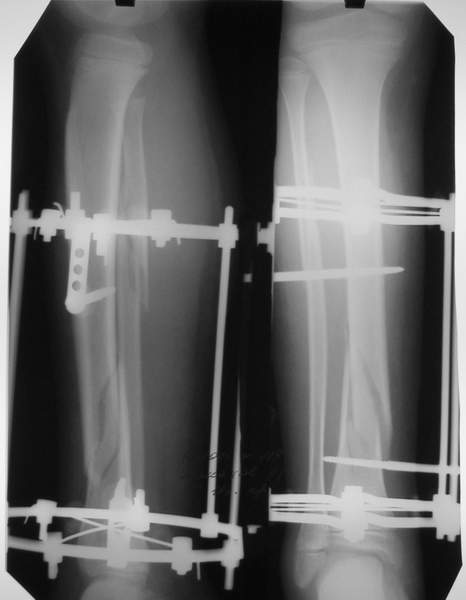

МТ мы используем, конечно, не только на голени. В прилагаемом примере у парня при поступлении была наружная ротация 40 гр. и "полумертвый" коленный сустав. Можно был бы, конечно, до конца использовать полную компоновку. Но для того он и есть метод выбора.